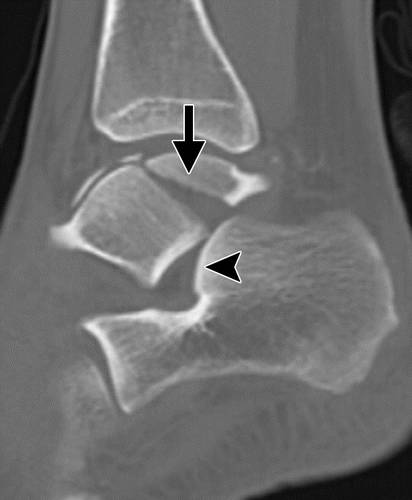

这种损伤必须与三角骨 - 一个附件后骨小梁区分开来。 在放射照相术中,后过程的断裂显示不规则的边缘(图13),而三角骨是圆形或椭圆形,具有光滑的皮质边缘(图14)。 双侧X线照片的价值有限,因为据报道三分之二的病例是双侧的(32)。 如果射线照片不确定,应进行CT。

图13b后突骨折。 (a)右足的外侧X光片显示在距骨后方的小骨质碎片(箭头)。 (b)右脚的轴向CT图像显示后路过程骨折(箭头)以及粉碎的程度和程度。